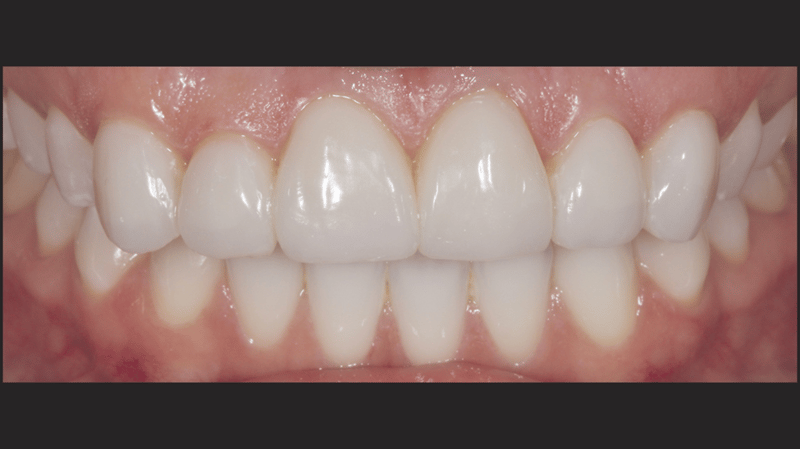

- Finale Restauration: Endgültige Zementierung mit einer stabilen und ästhetisch ansprechenden Veneer-Versorgung.

Mit dem durchgeführten Behandlungsprotokoll konnten die ästhetischen Anforderungen der Patientin erfüllt werden. Die Verfärbung der oberen Frontzähne wurde kaschiert und ein natürliches, auf die unteren Frontzähne abgestimmtes, Erscheinungsbild wurde erzielt. Die Verwendung von direkten Non-Prep-Kompositveneers war dabei eine konservative, höchst effektive Lösung, die sowohl den finanziellen Möglichkeiten der Patientin als auch ihrem Wunsch nach minimal-invasiven Methoden Rechnung trug.